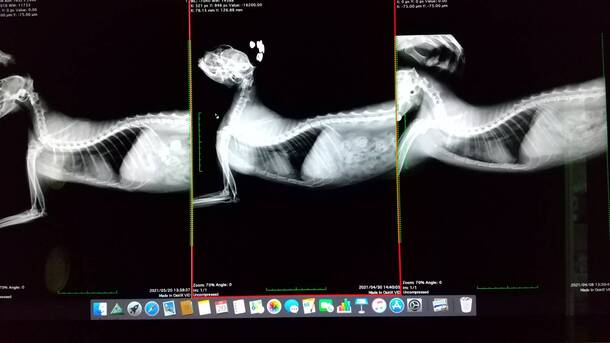

レントゲン写真

20日の病院に行ったときのぽんちゃんのレントゲン写真です。

ご支援頂いてる皆様のお陰で、ぽんちゃんの抗がん剤治療は、このまま順調に7月に入れば、月に一回になるって先生が言っておりました。